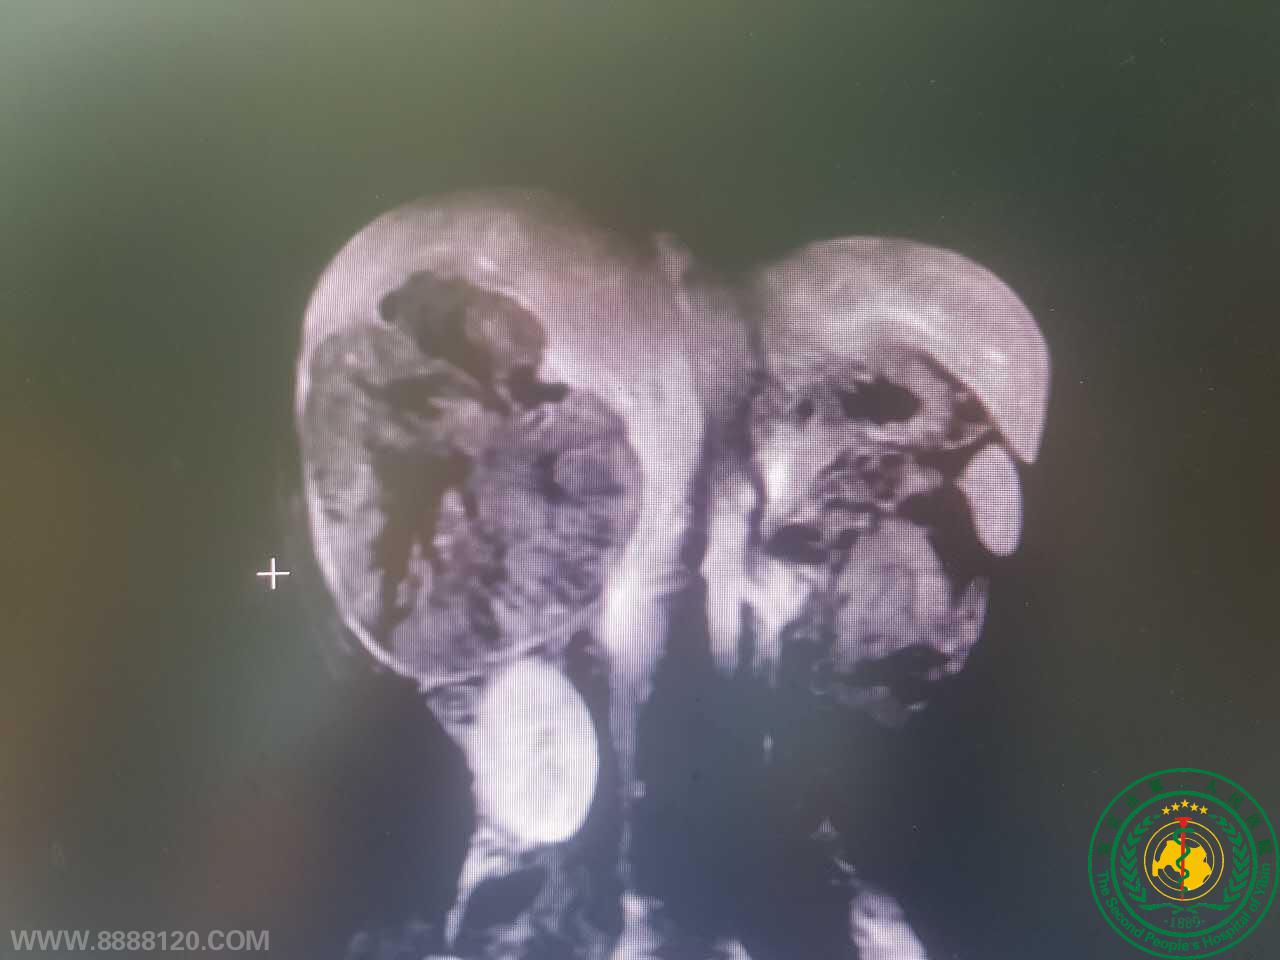

2017年08月07日,宜宾市二医院肝胆胰外科在麻醉科及手术室的配合下,为一例右肝巨大肝癌男性患者顺利完成了宜宾市第一例完全腹腔镜下前入路标准右半肝切除术。

术中采用精准断肝技术,未阻断全肝入肝血流,但出血少,未输血,对残肝功能影响降到最低。

采用前入路原位逆行切除方法,不需翻动挤压肝脏,降低了肿瘤播散转移风险。